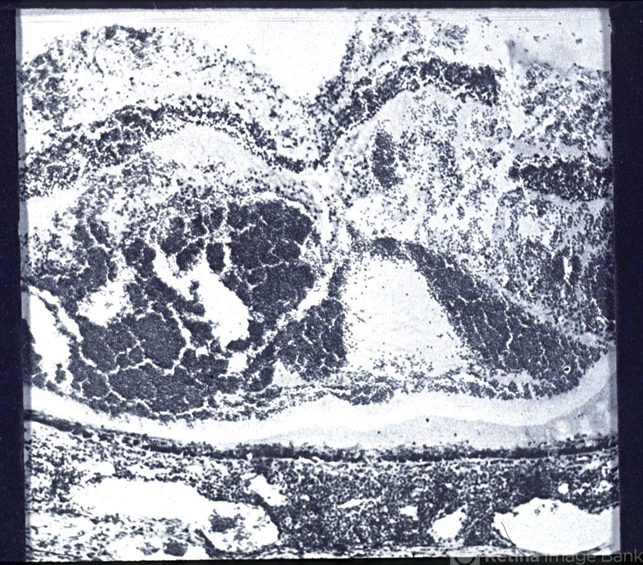

- histopathology, retinal necrosis

- Photomicrophotograph showing Hemorrhagic Necrosis involving all retinal layers